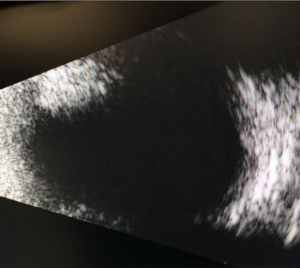

Slit lamp examination OD was remarkable for 2+ meibomian gland disease. Slit lamp examination OS was remarkable for 2+ meibomian gland disease, trace diffuse bulbar conjunctival injection, and trace bulbar conjunctival edema. The cornea had 3+ diffuse edema with guttata and 3 clock hours of pannus and neovascularization (Figure 1). The anterior chamber had a 1-mm tall hyphema (Figure 2) and anterior chamber reaction of 4+ cells and 1-2 flare. Clear and complete visualization of the iris was challenging due to the hyphema obstructing the inferior iris, 3+ corneal edema and 4+ cells and 1-2 flare anterior chamber reaction, making it difficult to completely rule out iris neovascularization. Posterior structures were also difficult to assess due to the corneal edema, hyphema and anterior chamber reaction. Therefore, a B-scan ultrasound was performed. No masses or retinal detachments were detected (Figure 3). Fundus examination and gonioscopy were performed only OD due to the presence of the hyphema OS. No abnormal vessels in the angles, angle neovascularization or other abnormalities were noted OD.

![]() Figure 2. Hyphema in the left eye present at initial visit. Click to enlarge |